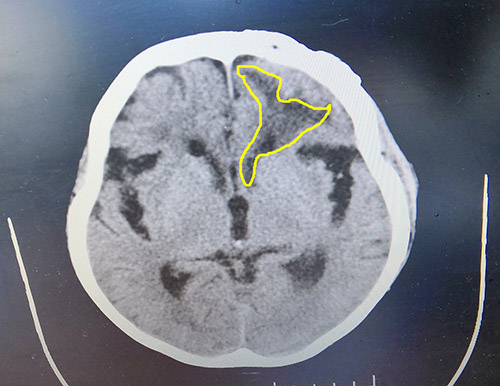

▲患者腦出血病灶區(qū)域

神經(jīng)外科6B病區(qū)主任詳細(xì)了解了王老太受傷、手術(shù)治療等情況,并為王老太完善相關(guān)檢查。頭顱CT顯示,左側(cè)額葉見(jiàn)不規(guī)則斑片狀低密度影,右側(cè)額葉小斑片狀低密度影;胸部CT顯示兩肺炎癥,兩側(cè)胸腔少量積液;患者頭部可見(jiàn)長(zhǎng)約15cm陳舊性手術(shù)切口,局部切口創(chuàng)面可見(jiàn)一約3cm×3cm大小破潰,表面可見(jiàn)少許白色分泌物;呼吸音粗,雙肺可聞及濕羅音,痰多且粘稠。